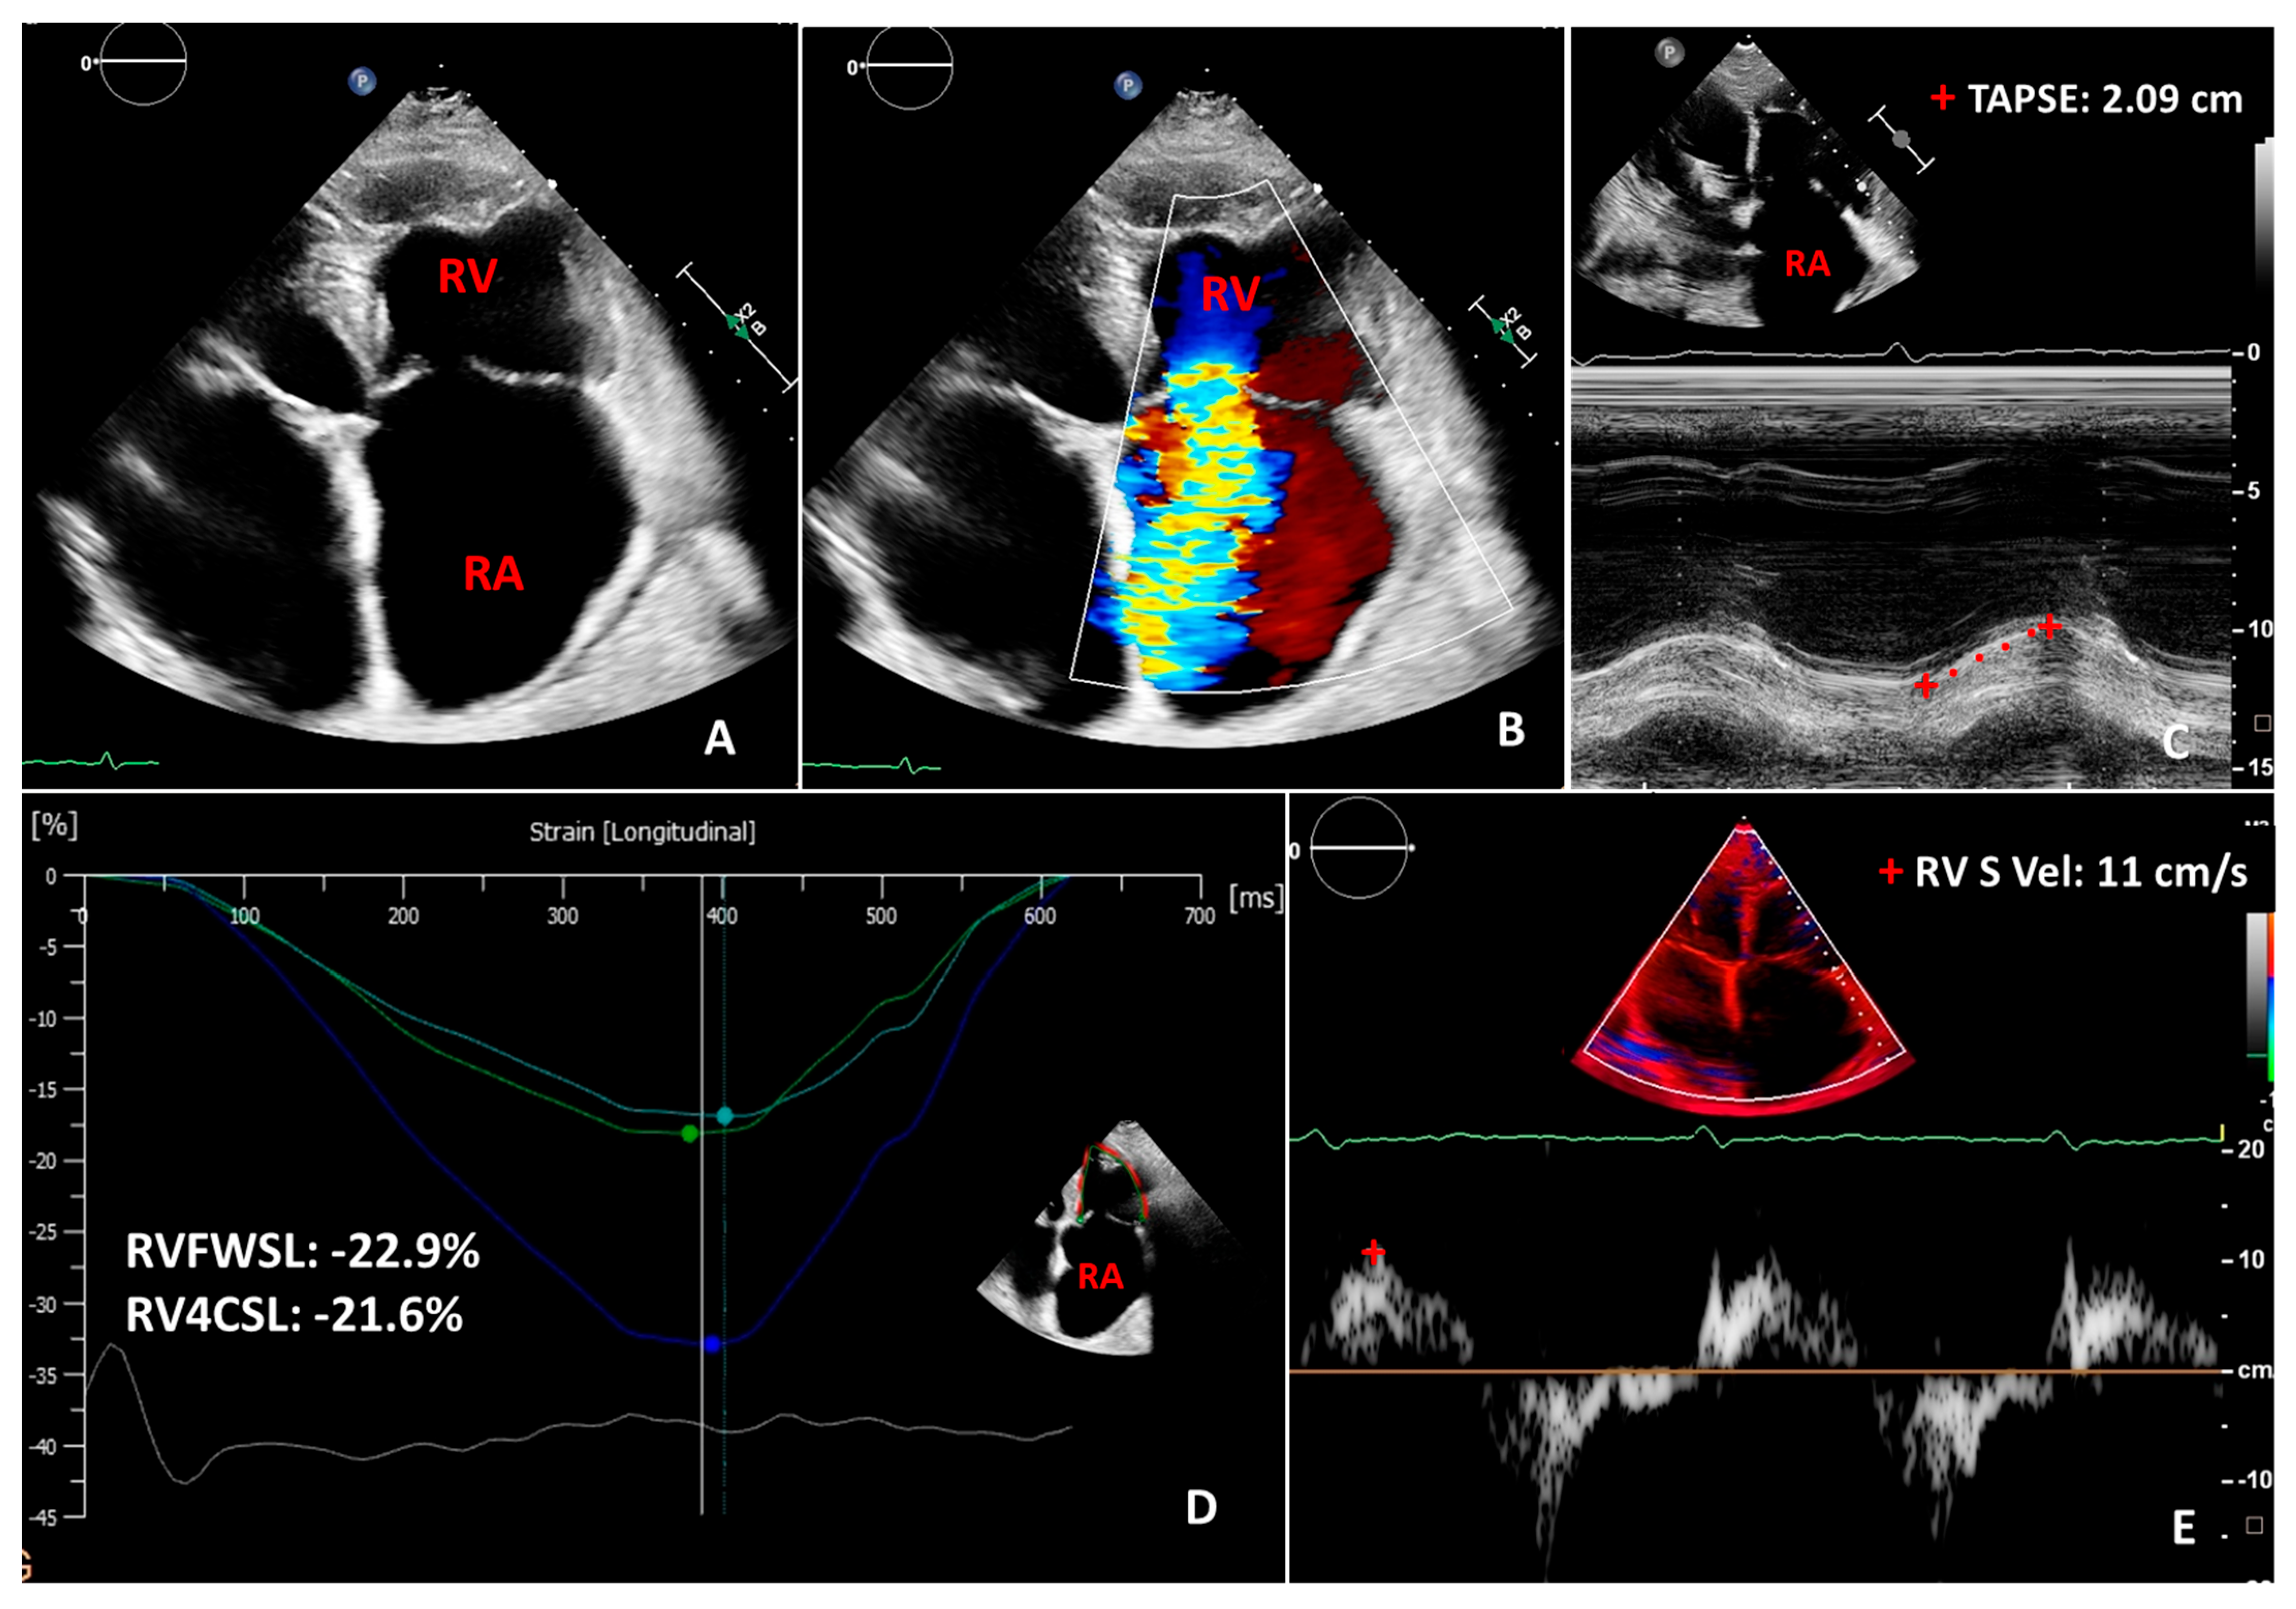

4. Two-Dimensional Echocardiography of the Right Ventricle and Tricuspid Valve

5. Three-Dimensional Echocardiography of the Right Ventricle and Tricuspid Valve